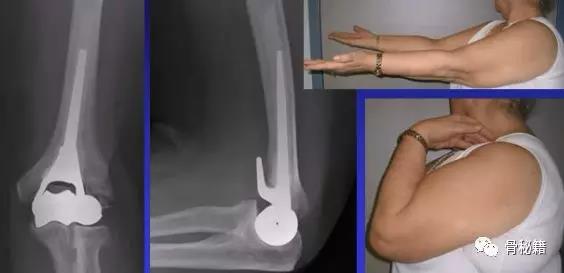

实在固定不了的时候,再进行肘关节置换术肘关节又分为半肘和全肘